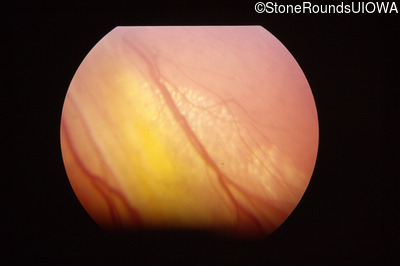

Visit at age: 15 years

Fundus Photography - Right - No Light Perception

Exemplar

Fundus Photography - Left - 20/25 +2